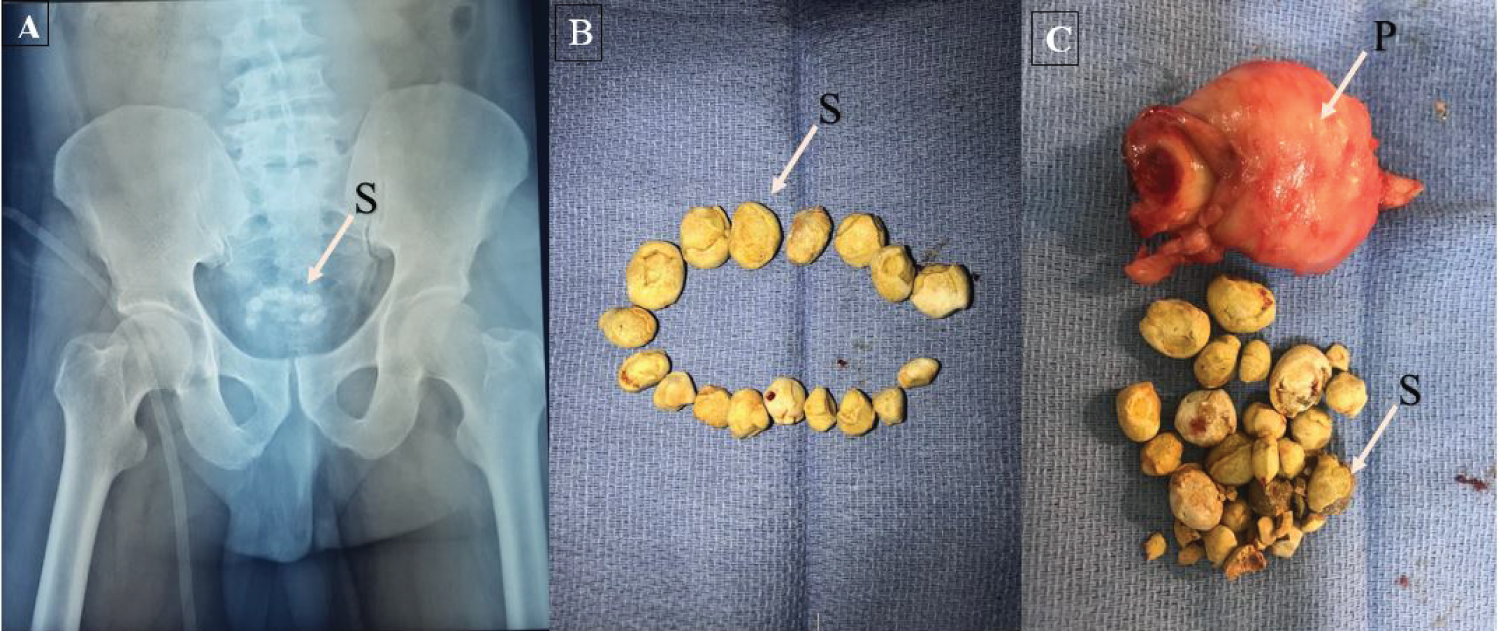

Multiple Stones In The Bladder MEDizzy Journal